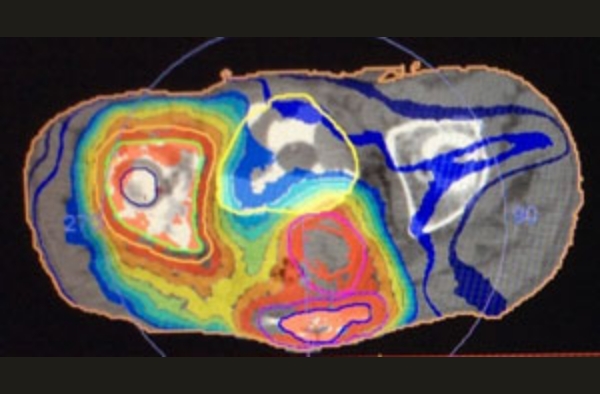

直腸がん+右骨転移